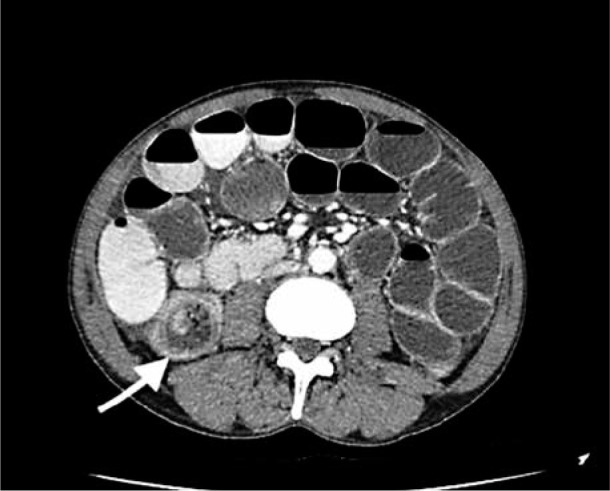

A case report of an idiopathic adult ileocolic intussusception.

特发性成人回结肠肠套叠病例报告。